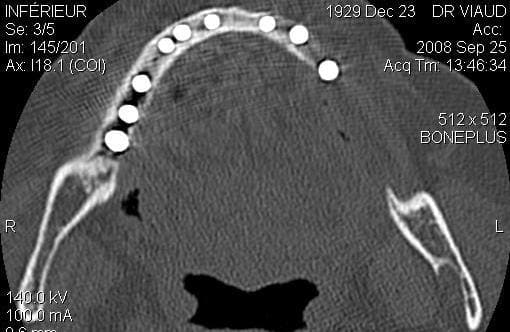

Pourquoi dis tu trop corticalisé?? Moi je ne trouve pas

Pour moi je pb c'est a chaque emplacement de couper ou les crosses même si elles ne sont que "sensitives" ça saigne bien et elles sont larges,

il me semble, que tu as une grosse partie corticale, sous l’artère et que le haut est très fin mais il est difficile d’interpréter une seule vue

je disais :pas d'expansion simple dans ce cas là trop corticalisé

par contre expansion complexe oui,